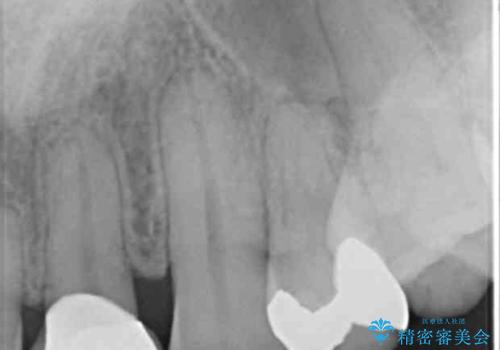

銀の詰め物を白くしたい セラミックインレーでの治療

- 銀歯が気になるためやり替えたいとのことで来院されました。

セラミックインレーで治療を行いました。

- 左上5 セラミックインレー 77,000円費用は治療当時の料金となります